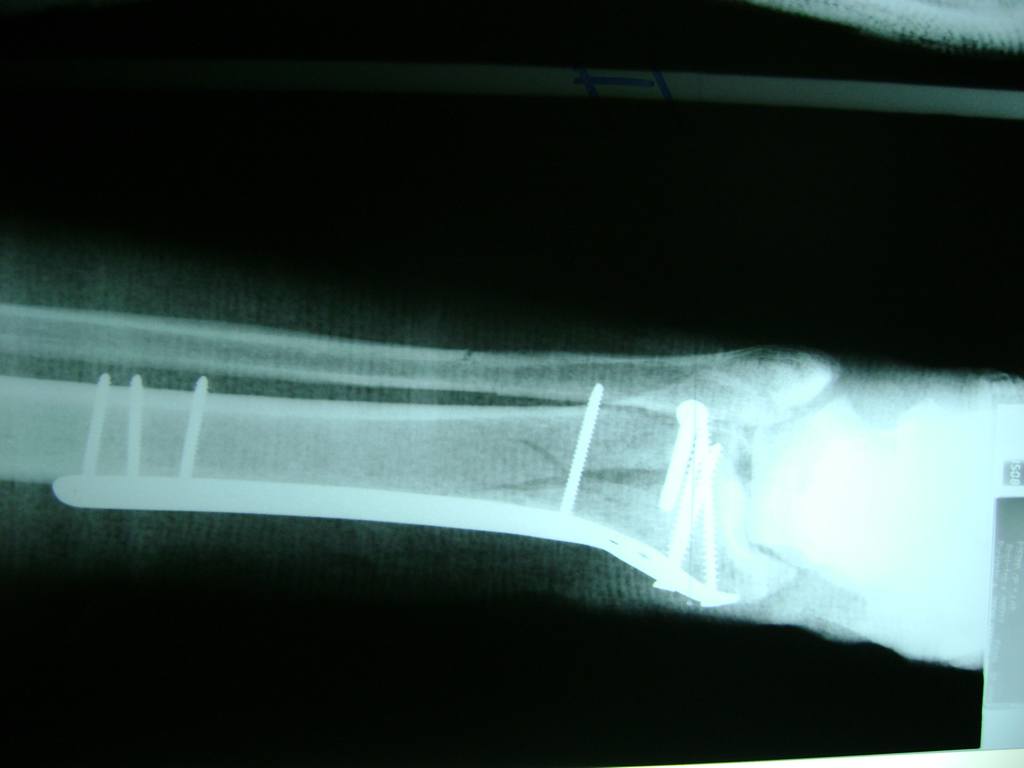

Cuando se necesita cirugía, es probable que esta implique el uso de clavijas de metal, tornillos o placas para sostener los huesos en su lugar mientras la fractura se consolida. Los elementos de soporte pueden ser temporales o permanentes.

Cirugía de Tobi...

Detail Download